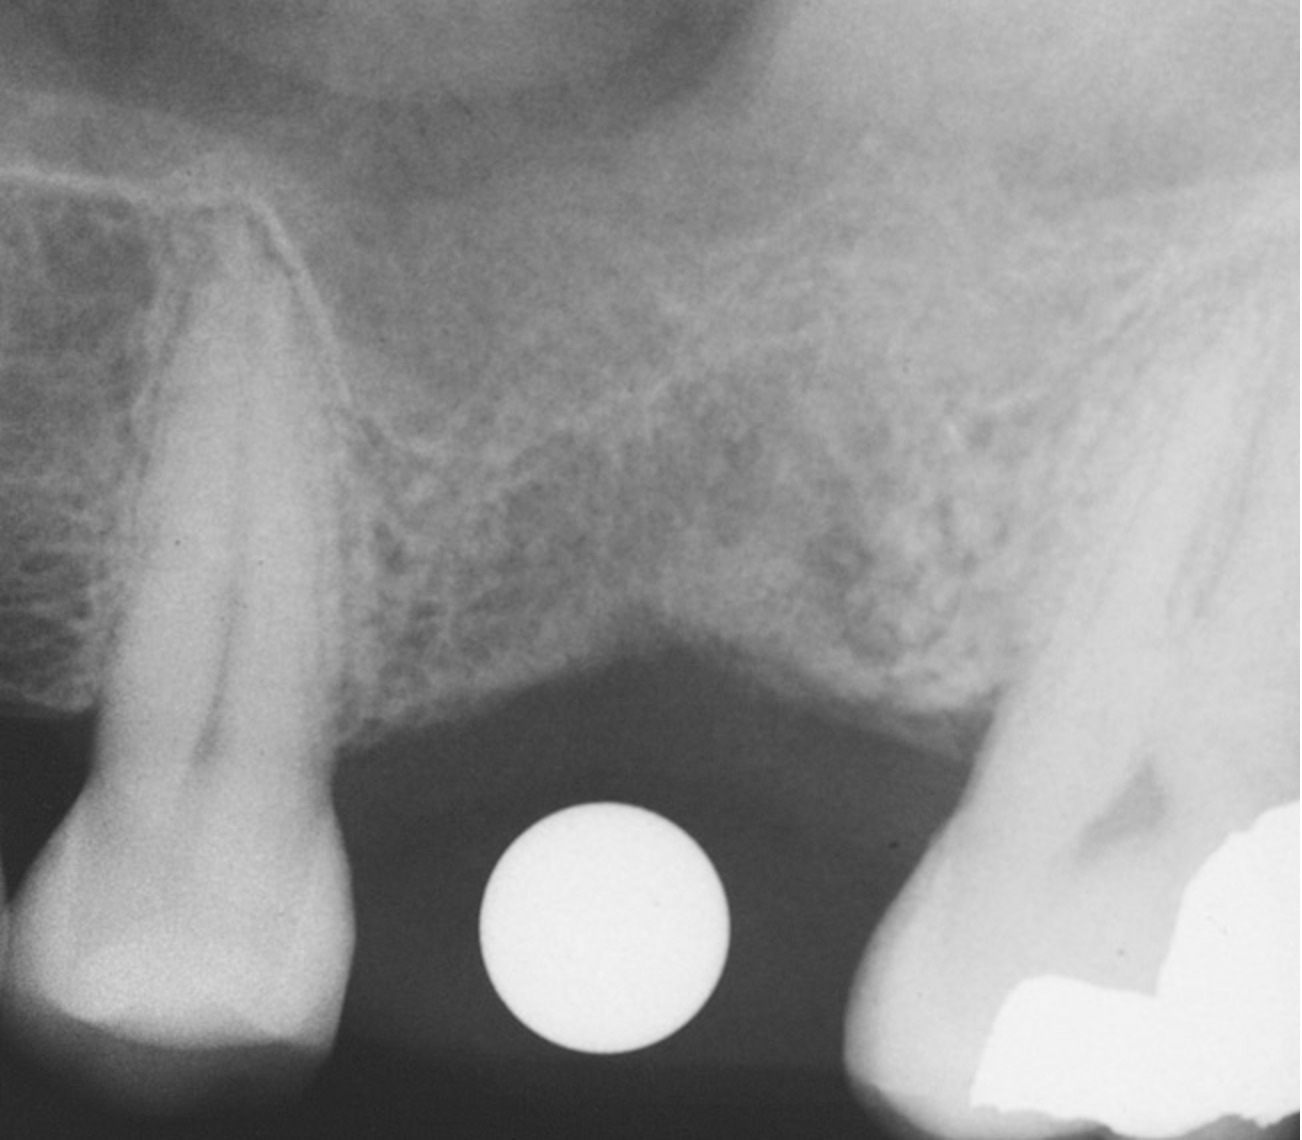

The sinus floor elevation technique can be used when a tooth is extracted and there is not enough bone height to support an immediate implant (Figure 8, Figure 9 and Figure 10, Figure 11).32

Figure 8  At site No. 13 the second bicuspid had a hopeless prognosis; it was to be extracted and replaced with an implant after a transcrestal sinus floor elevation.

Figure 8

Figure 9: After the extraction, a 2.1-mm twist drill was used to drill within 1 mm of the subantral floor. A guide pin was placed and a radiograph was taken to ascertain if the drill stopped within 1 mm of the subantral floor.

Figure 9